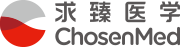

近日,求臻医学与青岛市中心医院放疗科张小涛主任合作,首次报道了一例有BRCA2胚系移码突变(NM_000059.3:exon11: c.4563_4564delAT: L1522fs)的难治性转移性纵隔卵黄囊瘤患者对局部放疗有显著反应。目前该案例报道(case report)已在线发表于Cancer Biology & Therapy(IF:4.742)。 研究背景 卵黄囊瘤,即内胚层窦瘤,是发生在卵黄囊内的高度侵袭性生殖细胞肿瘤。根据位置,可分为性腺卵黄囊瘤和性腺外卵黄囊瘤。性腺外卵黄囊瘤相对少见。它们通常发生在身体的中轴,如大脑、纵隔和腹膜后。纵隔卵黄囊瘤在婴儿期和青春期后更常见。 目前,卵黄囊瘤的标准治疗方案是博莱霉素(Bleomycin)、依托泊苷(Etoposide)和顺铂(Cisplatin)(BEP)化疗后进行手术。然而,由于恶性程度高,诊断时不可能完全切除,原发性纵隔卵黄囊瘤的预后极差,5年生存率为40%-50%,复发后仅仅有6个月的生存期。 过往研究表明,原发性纵隔卵黄囊瘤患者对化疗反应良好,但对放疗反应较差。据报道,某些病例对放射治疗敏感。 然而,目前对原发性纵隔卵黄囊瘤精准放疗的预测性生物标志物尚未被探索。 DNA损伤修复(DDR)对恶性和正常细胞的生存都至关重要。临床前数据显示,辐射敏感性与DDR有关。近期研究表明,DDR基因突变可能预测多种实体瘤患者对放疗敏感性增强。 本案例报告了一例难治性转移性原发性纵隔卵黄囊瘤男性患者。当患者接受化疗,同时使用或不使用特瑞普利单抗(Toripalimab, PD-1抗体)时,疾病进展迅速。然而,该患者对局部放疗很敏感。通过全外显子组测序(WES)在患者体内检测到了BRCA2胚系移码突变。 病例分享 上下滑动查看所有内容 病例讨论 放疗在纵隔卵黄囊瘤的治疗中起着至关重要的作用。为了最大限度地从放疗中获益,探索与疗效相关的生物标志物至关重要。以往的研究证明,包括BRCA1/2在内的DDR基因突变可能会增强多种实体瘤患者的放射敏感性。然而,DDR基因突变作为原发性纵隔卵黄囊瘤放疗的预测性生物标志物尚未被探索。 放射敏感性取决于多种因素,例如肿瘤组织学、辐射剂量和肿瘤细胞的固有放射敏感性等。其中肿瘤细胞的内在放射敏感性是最重要的因素。由于放疗主要通过产生DNA双链断裂(DSB)诱导细胞死亡,DDR无疑会影响肿瘤细胞的放射敏感性。 DDR系统通过八条途径修复多种形式的DNA损伤,以适当保护基因组的完整性。这八条途径包括错配修复(MMR)、碱基切除修复(BER)、核苷酸切除修复(NER)、同源重组修复(HRR)、非同源末端连接(NHEJ)、检查点因子(CPA)、范科尼贫血(FA)和易位DNA合成(TLS)。其中HRR和NHEJ通路负责修复DSB, BER负责修复单链断裂(SSB),MMR通路负责修复DNA插入/缺失。 BRCA1和BRCA2是介导HRR途径的两个关键分子。这两个基因的突变可能会破坏DSB的修复。由于辐射主要通过产生DNA双链断裂诱导细胞死亡, BRCA1或BRCA2突变的恶性肿瘤通常会导致HRR通路的缺陷,因此对电离辐射反应良好。 目前纵隔卵黄囊瘤的标准治疗方案是新辅助化疗后将残余肿块切除术。由于确诊时肿瘤通常巨大且常与邻近器官有纤维粘连,化疗后残余肿瘤的完全切除非常困难,也间接导致了本病较差的预后。新辅助化疗是纵隔卵黄囊瘤的主要治疗方法,初始治疗方案推荐以铂为基础的化疗,常用方案为4-6个周期的VIP(顺铂、依托泊苷和异环磷酰胺)或BEP。含铂方案化疗使高达50%的患者实现了长期生存。我们检索到了许多新辅助化疗后R0切除及术后达到病理学完全缓解(PCR)的报道。对于化疗和手术后复发的纵隔卵黄囊瘤患者,再次化疗的效果很差。本例患者对化疗不敏感,原因尚不明确。 此外,患者对免疫检查点抑制剂(ICI)治疗不耐受。可能与患者MSI-L、TNB-L和HLA LOH强阳性有关(表1)。HLA LOH强阳性意味着HLA-A、B和C三个基因同时缺失。HLA LOH是免疫逃逸的常见原因。这是由于抗原提呈细胞通过HLA I类分子的抗原提呈新抗原在细胞免疫中起着关键作用。HLA-LOH导致抗原呈递减少,从而促进了免疫逃逸。 此前的研究表明,BRCA1突变的携带者患乳腺癌、卵巢癌、前列腺癌和结肠癌的风险增加,而BRCA2突变的携带者患男性乳腺癌、胰腺癌和前列腺癌的风险更高。目前卵黄囊瘤的发病机制尚不清楚。然而,该患者的BRCA2胚系移码突变应该与其病因密切相关。BRCA2胚系突变导致负责DSB修复的HRR通路缺陷。 PARP抑制剂可能抑制PARP-1介导的SSB修复(即BER通路),从而增加DNA链断裂的积累,促进基因组不稳定性和细胞凋亡。根据合成致死率的概念,PARP抑制剂可以有效地摧毁BRCA基因缺陷的肿瘤以及同源重组能力较低的睾丸肿瘤细胞系。迄今为止,FDA已批准奥拉帕利用于治疗BRCA胚系突变的卵巢癌、乳腺癌和前列腺癌。此外,奥拉帕利在治疗BRCA胚系突变的胰腺癌和小细胞肺癌(SCLC)方面也表现出显著的临床疗效。 此外,Yue Bi等人的一项研究表明,奥拉帕利作为一种有效的放射增敏剂,在BRCA1缺陷型高级别浆液性卵巢癌的临床前模型中具有潜在的应用价值。这使我们联想到PARP抑制剂可能被用作潜在的放射增敏剂,以提高BRCA2突变患者的放疗敏感性。正如所料,本案例中的患者对局部放疗联合奥拉帕利治疗表现出良好的反应。 结论与启发 该病例报告首次描述了一例BRCA2胚系移码突变的难治性转移性纵隔卵黄囊瘤患者对放疗具有显著反应,可为临床实践中的精确放疗提供有见地的线索。